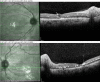

Bilateral Lupus Chorioretinopathy in a Patient With Active Systemic Lupus Erythematosus

Ocular involvement is commonly seen in systemic lupus erythematosus (SLE). However, chorioretinopathy is an easily missed ocular manifestation of SLE. Early recognition and a multidisciplinary treatment approach can play a key role in reducing the ocular and systemic morbidity seen with this condition. This case report describes a patient with active SLE who presented with bilateral lupus chorioretinopathy. The patient demonstrated a significant improvement in ocular symptoms once the systemic disease was controlled.